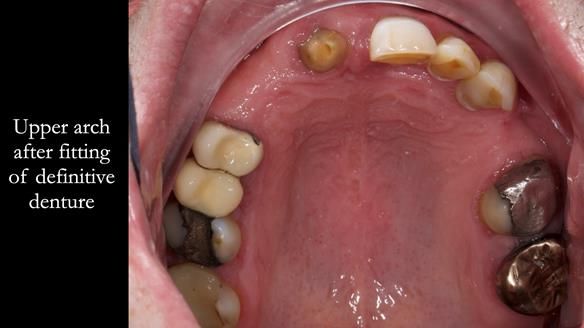

Treatment Process: I provided the clinical work, while Rowan Garstang handled the technical work. The treatment required five visits to fit the RPD. The worn lower anterior teeth were then built up. Unfortunately, I did not check the guidance on the denture teeth after this, and tooth 11 fractured off the denture. Brian was very understanding, and I adjusted the denture thoroughly. It has been fracture-resistant and trouble-free for the last three years.